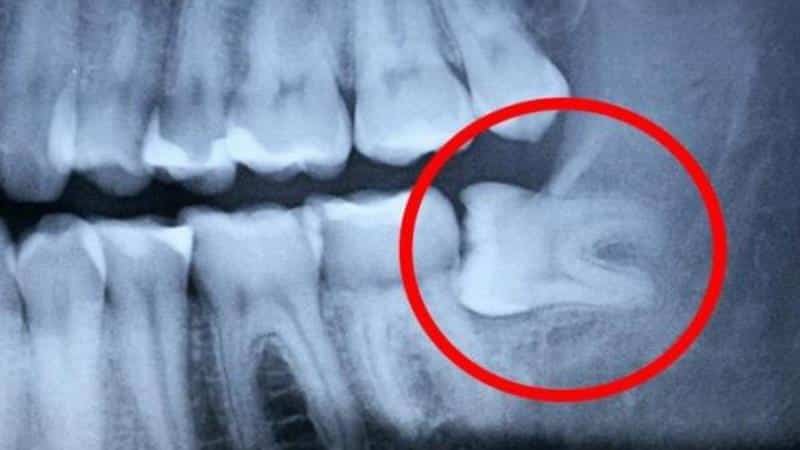

Если зуб мудрости начинает расти во время беременности, рекомендуется сделать рентгеновский снимок, чтобы специалист мог оценить ситуацию. Вмешательство требуется, если у женщины возникают следующие симптомы:

Стоматологические процедуры рекомендуется проводить во втором триместре беременности. Специалист принимает решение о неотложном или плановом удалении зуба мудрости, если пациентка жалуется на перечисленные симптомы. При этом используется местное обезболивание. Современные медикаменты для местного применения безопасны для женщины, однако наилучшее время для проведения процедуры — второй триместр беременности. В это время иммунитет женщины укреплен, а риск для ребенка минимален. Нежелательно проводить манипуляции на первом, третьем и девятом месяце беременности. Чтобы избежать нежелательных последствий, рекомендуется заботиться о здоровье зубов еще до зачатия.

Будущим мамам следует знать, как не следует поступать, если у них возникают проблемы с положением зуба мудрости. Вместо того чтобы прикладывать обезболивающие таблетки к болезненному месту, лучше обратиться к врачу, чтобы избежать воспаления слизистой и ран. Также не рекомендуется прогревать патологическое место грелкой или использовать горячие настои для полосканий, так как это может способствовать размножению бактерий. Самодиагностика и самолечение также не рекомендуются. Лучше обратиться к врачу, чтобы получить точный диагноз на основе рентгенологического исследования.